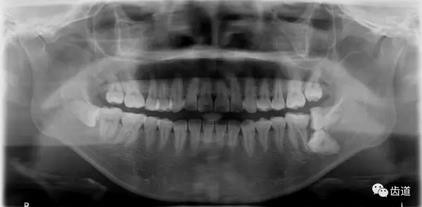

五)口腔正畸

CBCT在頜骨正畸科方面的應(yīng)用:軟件功能的強大,提供有效的數(shù)據(jù),為頜骨正畸提供了極大的幫助,免除了很多臨床醫(yī)生的手工繪圖,并有利于科研、教學(xué)等方面發(fā)展研究。

投影測量側(cè)位片影像